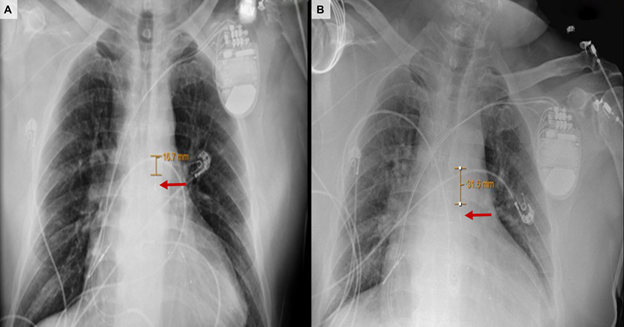

Ambulation was successful with no femoral complications (Figure 3; Videos 1, 2), and a post-ambulation chest x-ray was performed to reassess the position of the TF-IABP, which in this case was repositioned at the bedside (Figure 4). Post-transplant, the patient was able to successfully discharge home without need for inpatient rehabilitation.